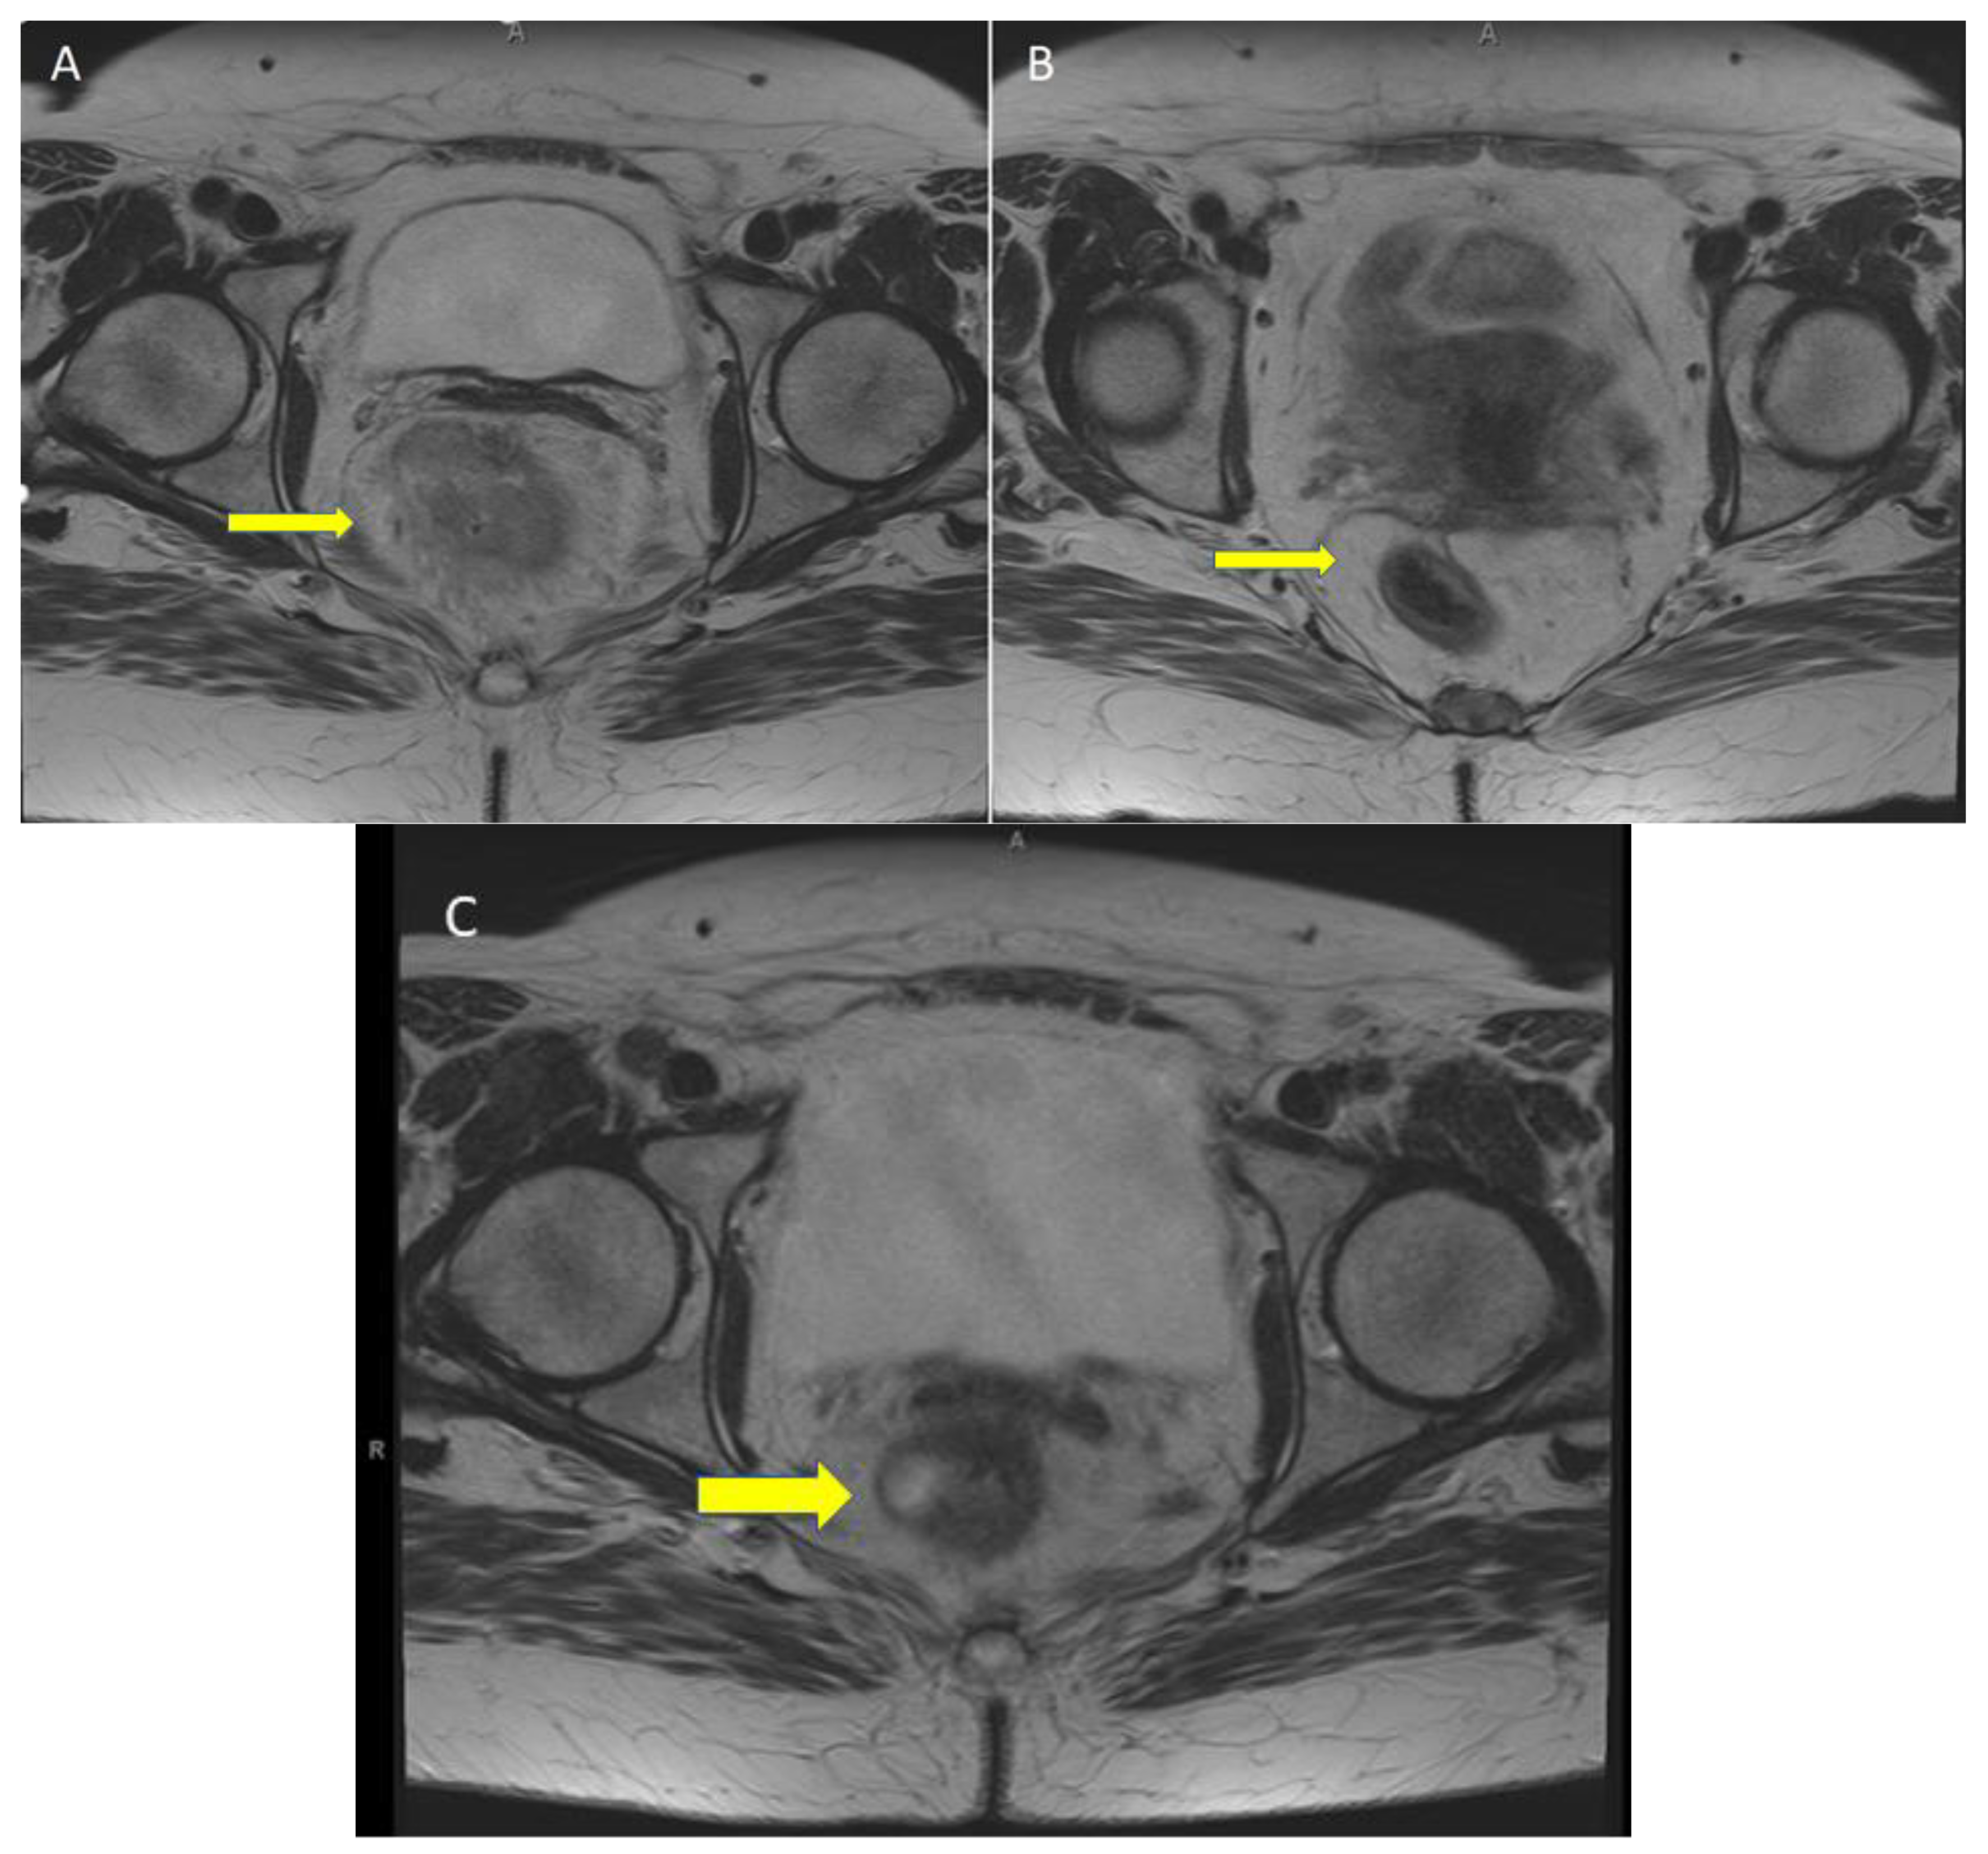

4. Current Management of dMMR Rectal Cancer

5. Case Report: ICI with Total Remission in dMMR laRC after a Single Cycle

6. ICI Toxicity Management

7. Response Assessment and Management of Immunotherapy-Related Rectal Stricture